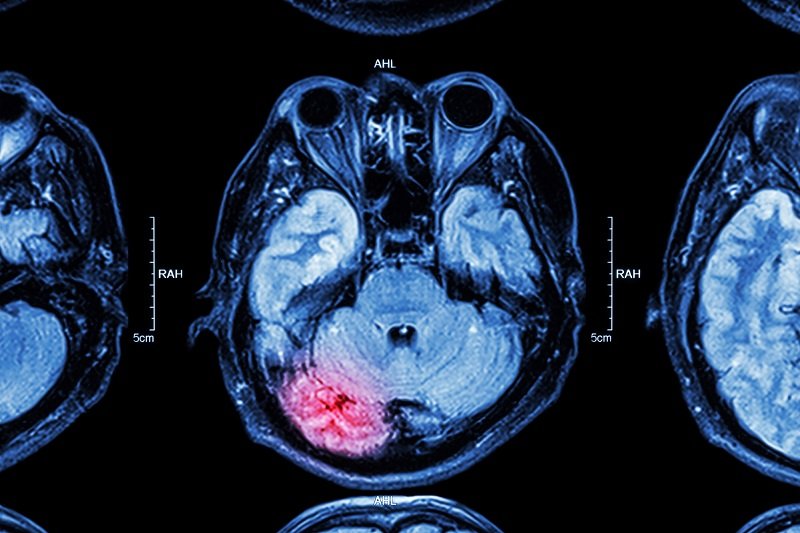

© Depositphotos - Нарушение мозговой деятельности

Причиной тремора в некоторых случаях может стать инсульт или черепно-мозговая травма. Справиться с проблемой поможет медикаментозное лечение в сочетании с отказом от кофеина, никотина и алкоголя.